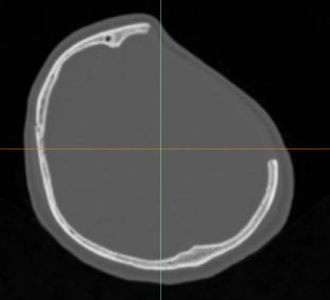

術(shù)前診斷:左側(cè)額顳部顱骨缺損

術(shù)前影像

左側(cè)額顳部顱骨缺損